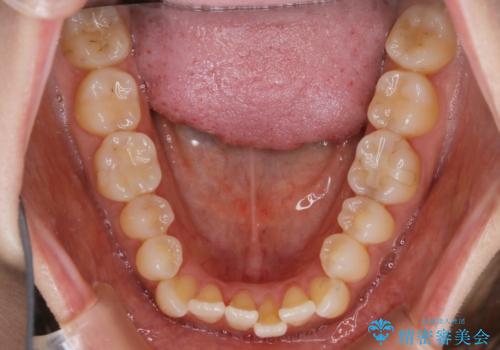

【非抜歯】短期間で実現する前歯の反対咬合治療

- 前歯のガタつきを主訴に来院されました。

奥歯の噛み合わせにはほとんど問題が見られず、歯列拡大とIPRのみの必要最低限の移動で歯並びの治療を計画することとなりました。

拡大とIPR

歯列の幅を拡大することにより作れるスペースは想像より大きく、実際に拡大だけでガタつきが治せるというケースもあります。

その他の歯のガタつきをとるためのスペース作りの方法の一つにディスキング(IPR)という方法があります。

歯と歯の間を一ケ所あたり最大0.5mmまでの範囲内で削ることで歯自体が少し小さくなり、それにより作られるスペースを数ヶ所分合わせることで合計で数mmの大きなスペースが作れるという方法です。